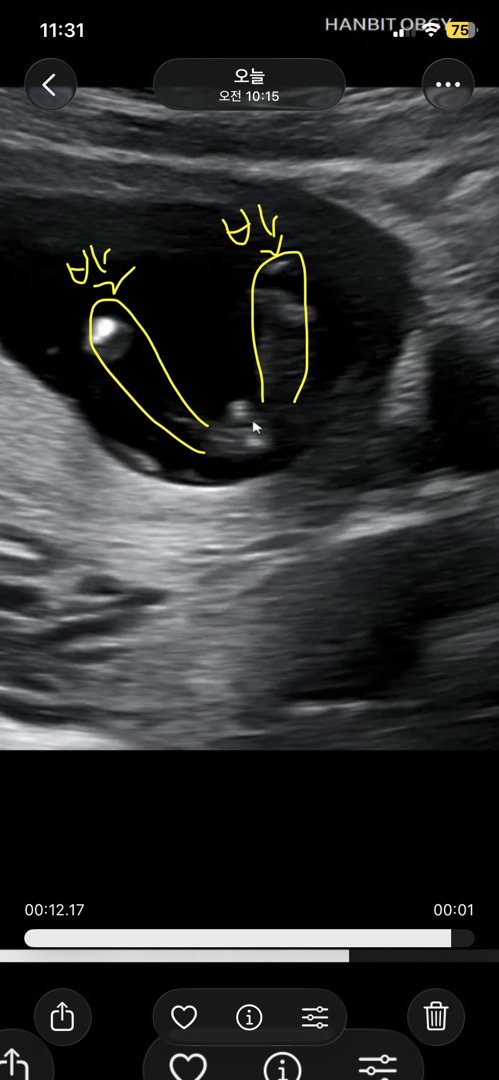

13주6일 다리사이 사진 봐주세요

선생님이 자꾸 뭐가 보인다고 콕 찝어주셨어요 이 시기면 반전없겠죠?! 🥹🥹

네!! 남아 같아요💙